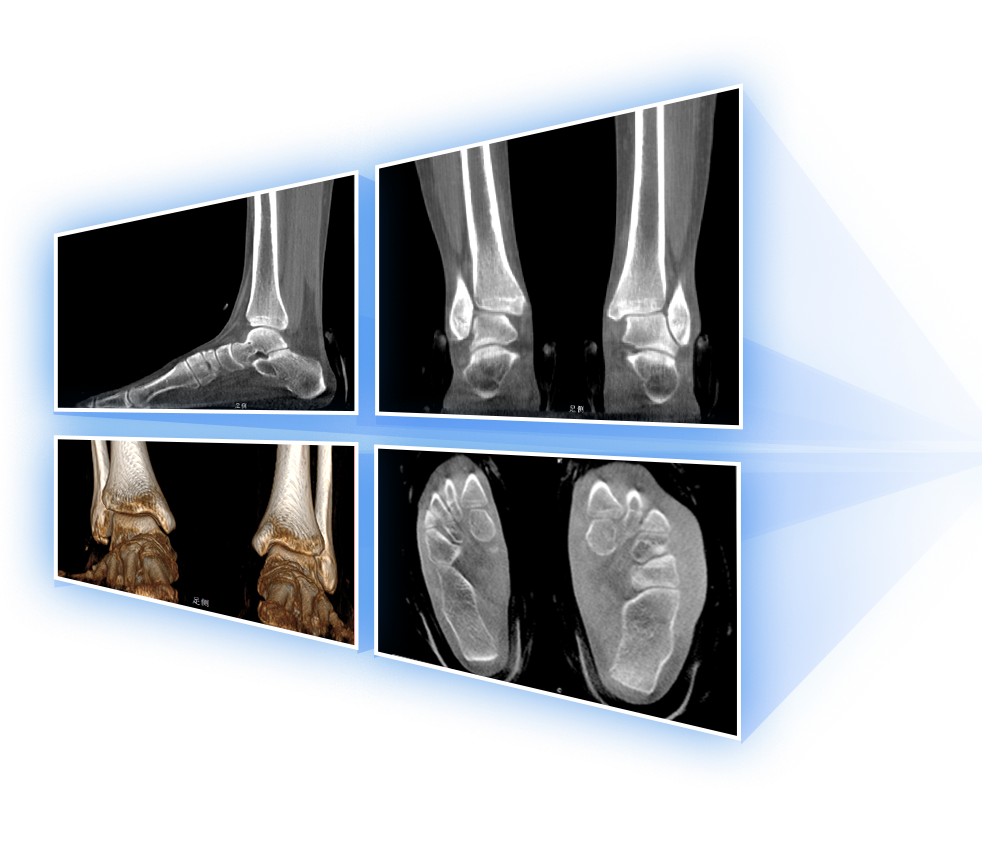

足踝

VR體繪制重建